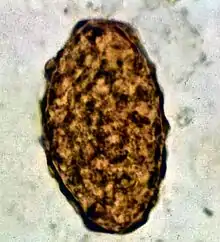

Ascaris lumbricoides is characterized by its great size. Males are 2–4 mm (0.08–0.2 in) in diameter and 15–31 cm (5.9–12 in) long. The male's posterior end is curved ventrally and has a bluntly pointed tail. Females are 3–6 mm (0.1–0.2 in) wide and 20–49 cm (7.9–19 in) long. The vulva is located in the anterior end and accounts for about one-third of its body length. Uteri may contain up to 27 million eggs at a time, with 200,000 being laid per day. Fertilized eggs are oval to round in shape and are 45–75 μm (0.0018–0.0030 in) long and 35–50 μm (0.0014–0.0020 in) wide with a thick outer shell. Unfertilized eggs measure 88–94 μm (0.0035–0.0037 in) long and 44 μm (0.0017 in) wide.[9]